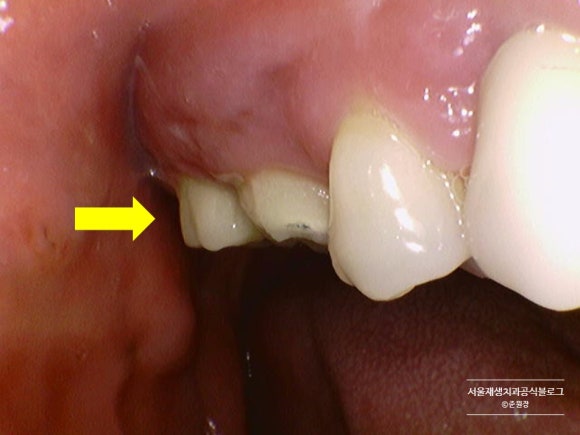

임플란트 머리 윗부분까지

퉁퉁 부어오른 잇몸이 보이시나요?

오랫동안 고생을 많이 하신 것 같습니다.

임플란트 주위 염증치료나,

잇몸치료로 개선될 수 있는 정도를 넘어선 상태여서

어쩔 수 없이 발치를 권해드렸습니다.

늘 염증이 자주 생기고 불편했던 임플란트라고 하시더군요.

지속적인 임플란트 주위염증이 이렇듯 파괴적인 치조골 흡수로 연결된다는 것을 보여주는 교과서적인 사례라고 생각됩니다.

임플란트 뿌리에 덕지덕지 붙은 염증조직들이 보이시나요?